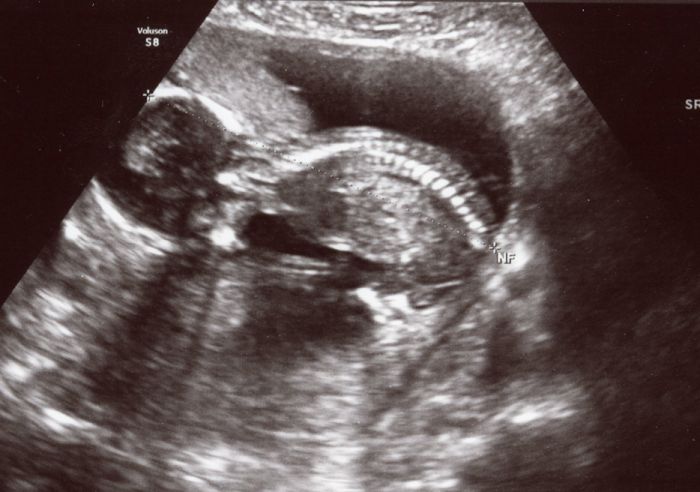

No a já jsem byla včera na prohlídce a je všechno v pořádku. Prcek se bohužel neukázal, tak zatím nevím, co to bude. Dr. ho změřil na cca 10cm. Dle ms jsem byla včera 15+4 a dle velikosti miminka jsem asi 16+2, takže povyrostlo ;-) Moje břicho taky podle toho vypadá!!! Ale už na to kašlu, nezakrývám, spíš ještě víc vystrkuju :-D Za 2 týdny jdem na UZ zas, kde nám doktor natočí video a snad už se prcek umoudří a ukáže nám, co má mezi nohama ;-) Jinak jsem si teda nechala odebrat krev na tripl test, ale doktor mě ujistil, že pro něj směrodatný je NT screening, a že patří mezi poslední, kdo by mě chtěl posílat na odběr plodovky. Tak nás tím celkem uklidnil. Nicméně tyhle výsledky mě už ani nezajímaj, tak se po nich ani nebudu pídit.

Tady je fotečka.

Jéé Blani to je srandovní to vypadá jak nějaký zviřátko :-) jak to tam má ty obratlíčky:-)